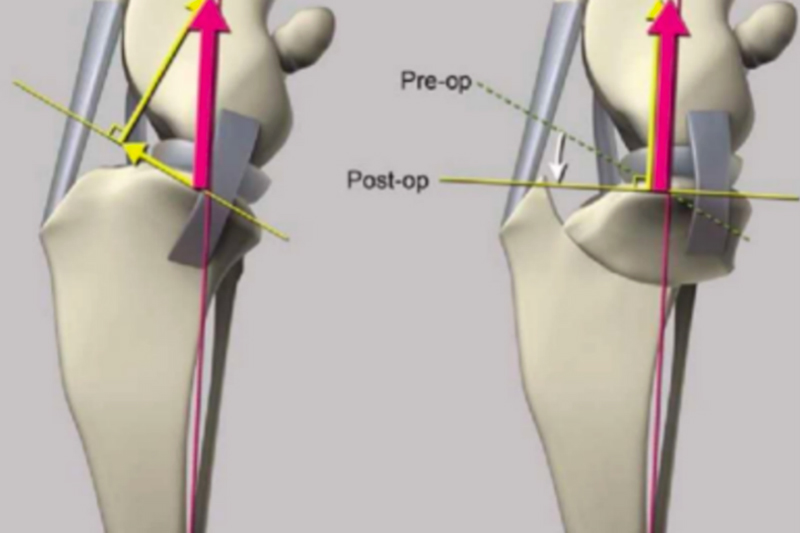

Figure 1 Preoperative CR image

The hemilaminectomy site was redefined preoperatively based on plain X-rays (Figures 1 and 2). Surgical approach: A single incision of the skin and subcutaneous fat was made parallel to the dorsal midline, offset 1 cm (Figure 3). The lumbar multifidus muscle attached to each spinous process was exposed using a scalpel. The lumbar multifidus muscle was then bluntly dissected from the lamina using a periosteal elevator until it reached the facet articular processes (Figure 4). One or two articular processes were dissected in sequence, anterior and posterior to the affected area, and the surrounding tissue was completely separated from the bone to fully expose the articular processes. A rongeur was used to create a bite mark in the lamina anterior and posterior to the affected area, with repeated manipulations to deepen the mark. When cancellous bone was visible (Figure 6) and the dura mater was visualized, the rongeur was discontinued and replaced with a nucleus pulposus forceps, carefully removing the bone from the lamina to expose the medullary cavity. The rongeur and nucleus pulposus forceps were then used alternately to remove the affected articular processes, further exposing the medullary cavity (Figures 7 and 8). After the main surgery, the wound is irrigated, blood clots and bone fragments are removed, a fat pad is placed on the exposed medullary cavity, the lumbar muscles are repositioned, and the dorsal fascia is sutured. The skin tissue is closed routinely.